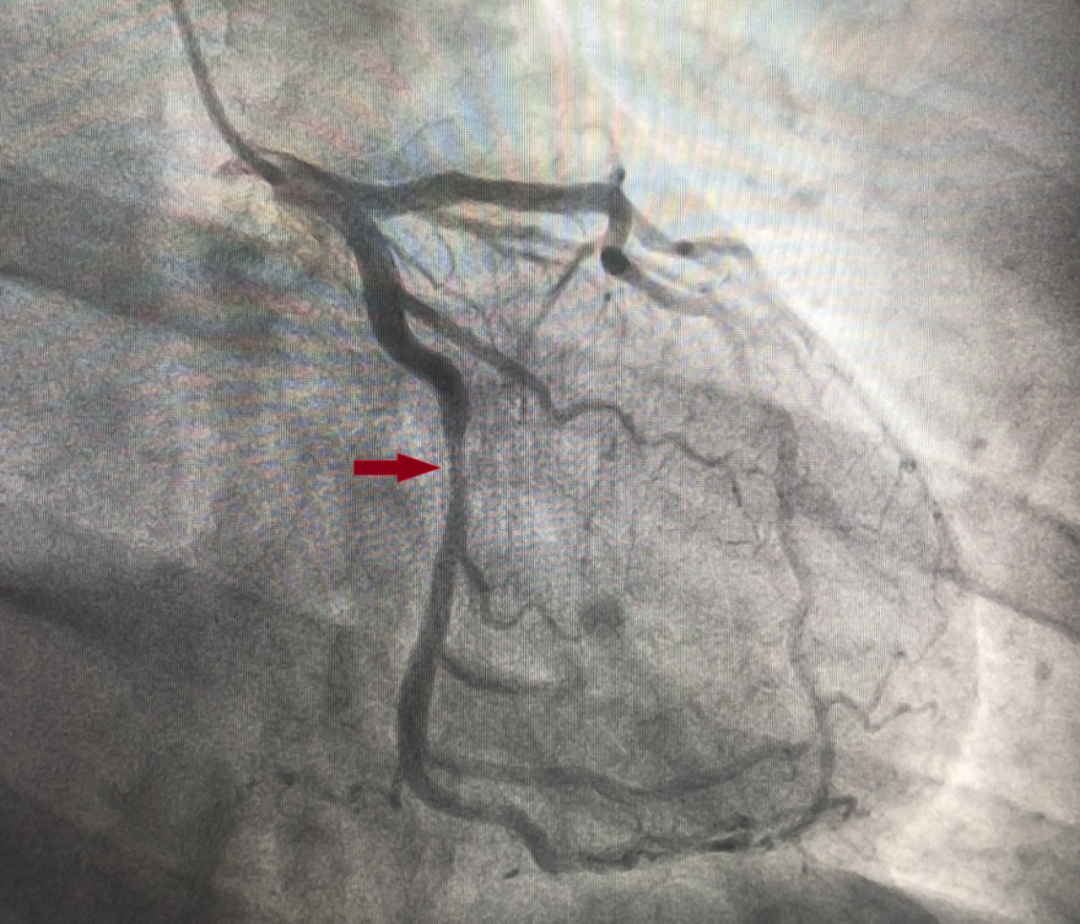

术中赵军礼主任带领介入团队严格遵循操作规范,使用切割球囊、非顺应性球囊对靶病变进行充分预处理,准确测量靶血管直径。造影显示患者病变较长,需要串联植入2枚BRS才能完全覆盖病变,但BRS支架梁较厚,串联植入既不能重叠,又不能留有空隙,与传统的药物洗脱支架植入要求完全不同,故技术难度较大。

介入团队成员经深思熟虑,制定手术策略后,选择合适尺寸的支架并精准定位后,顺利串联植入可吸收支架。术后王先生心绞痛的症状明显缓解。